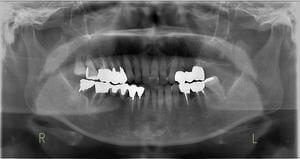

虫歯の治療、矯正の相談をご希望され来院されました。お口の中を診査(レントゲン写真、口腔内写真、視診)させていただいたところ、虫歯については問題なくきれいに歯磨きされているようでした。 正面から見るとジグザグしており、お口 […]

全体的な歯並びの矯正治療を行いました。治療期間は3年間。

ジグザグの歯並びを気にされてご来院されました。. 見た目の問題も大切ですが、それ以上に清掃がしにくいために虫歯・歯周病に非常になりやすく、不正咬合(良くないかみ合わせ)は顎の関節に負担をかけてしまい顎関節症を引き起こす可 […]

歯の大きさに対する顎の大きさのスペース不足により歯が並びきらず、ジグザグの歯並びおよび上の前歯が出っ歯になっていました。 左右4番の歯を抜歯することにより歯を並べるスペースを確保し、歯並びを揃えました。 全体の歯並びが綺 […]